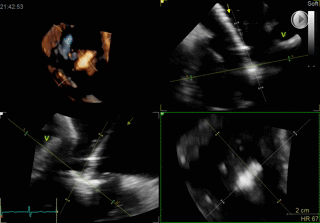

TAVI

- Paravalvular Leak After Transcatheter Aortic Valve Replacement. The New Achilles’ Heel? A Comprehensive Review of the Literature - https://www.ncbi.nlm.nih.gov/pubmed/23375925

- Aortic regurgitation after transcatheter aortic valve implantation: mechanisms and implications. http://cdt.amegroups.com/article/view/1552/2256

- 5-year outcomes of transcatheter aortic valve replacement or surgical aortic valve replacement for high surgical risk patients with aortic stenosis (PARTNER 1): a randomised controlled trial - https://www.ncbi.nlm.nih.gov/pubmed/25788234